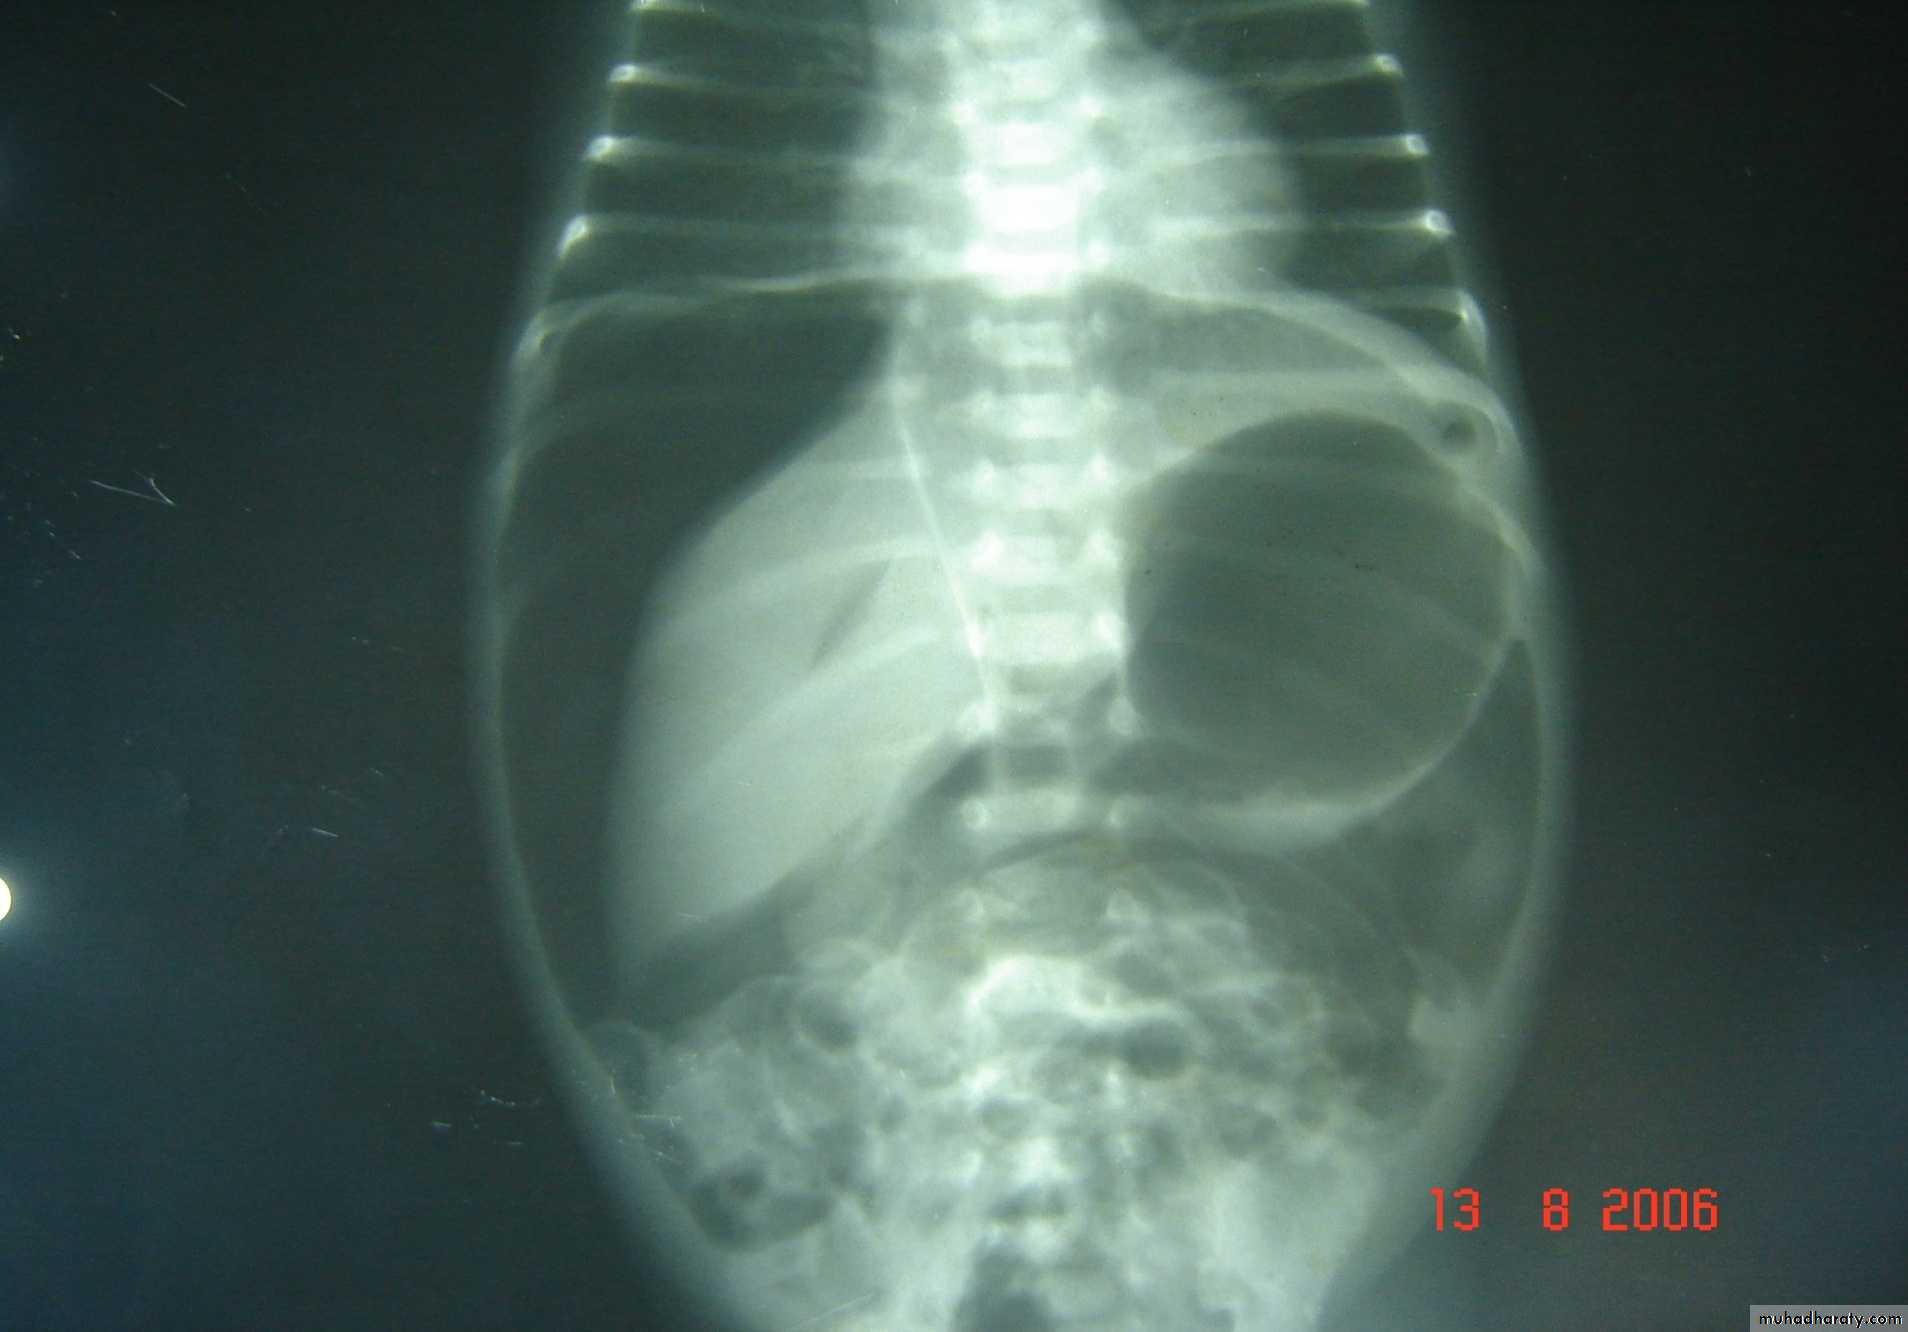

Necrotizing enterocolitis(NEC):

gastric retention (frequently bilious), distention & occult or bright red bd in stool, should raise concern. Although this disease usually occurs in premature infants, it also may occur in full-term infants.

Abdominal XR: pneumatosis intestinalis, gas in the portal vein, or free intraperitoneal gas(pneumoperitoneum) supports Dx.

pneumoperitoneum